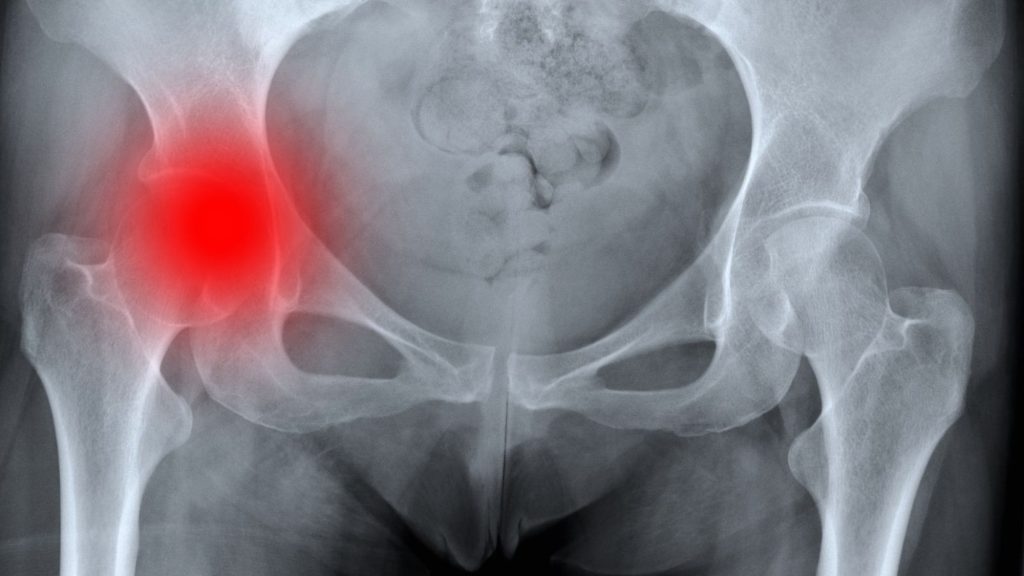

Bir yaşlı düşme sonrası kasığında veya kalçasında şiddetli ağrı hissediyor, ayağının üzerine basamıyor ve o bacağı diğerine göre daha kısa veya dışa dönük duruyorsa, kalça kırığı şüphesi çok yüksektir. Böyle bir durumda zaman kaybetmeden tam teşekküllü bir sağlık kuruluşuna başvurulmalıdır. Acil serviste yapılan röntgen çekimleri ve gerekli durumlarda tomografi tetkikleri ile kırığın tipi ve yerleşimi netleştirilir.